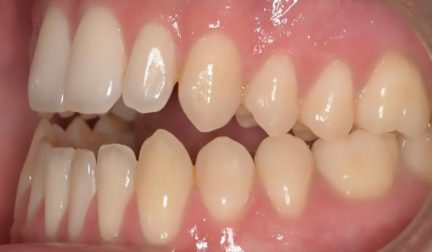

Classe III, béance, arcades étroites, arcades asymétriques, déviation médiane maxillaire, déviation médiane mandibulaire, décalage médian, encombrement, rotations, espacement, diastème

- Surplomb et recouvrement normaux obtenus

- Surplomb amélioré

- Amélioration significative du surplomb

- Taquets d'égression optimisés au niveau des incisives supérieures et inférieures et des canines: fermeture à béance ouverte antérieure.

État initial

État final